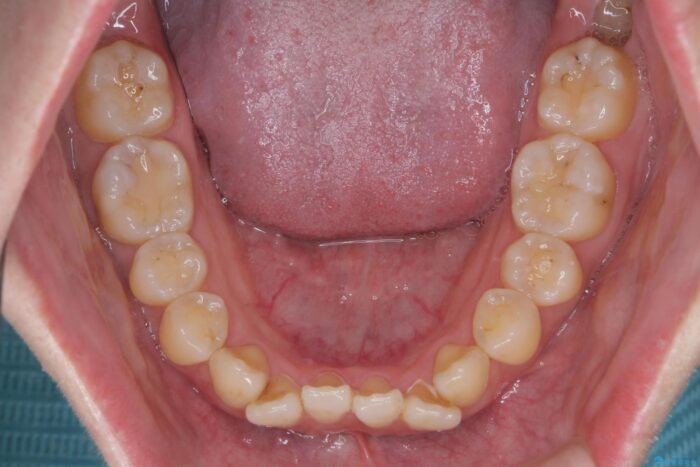

前歯のねじれが気になる、歯並びを改善したいとご来院された患者様です。

歯のねじれをきれいに取るのは、インビザライン(マウスピース矯正)だけでは難しい動きです。そのため、事前に4か月間の部分ワイヤー矯正を行い、治療期間を短くし、より美しい仕上がりを目指す計画です。

前歯が綺麗に並び、大変ご満足いただけました。